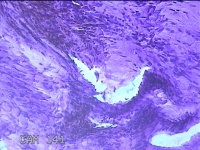

右侧中指尺侧包块

性别

女

年龄

53岁

临床诊断

肌腱腱鞘囊肿

一般病史

发现右侧中指尺侧一包块1年余,无明显疼痛及不适。

标本名称

大体所见

灰白暗红色肿物1.2x0.8x0.3cm一个,表面糜烂,切面灰白粉红色,质软。